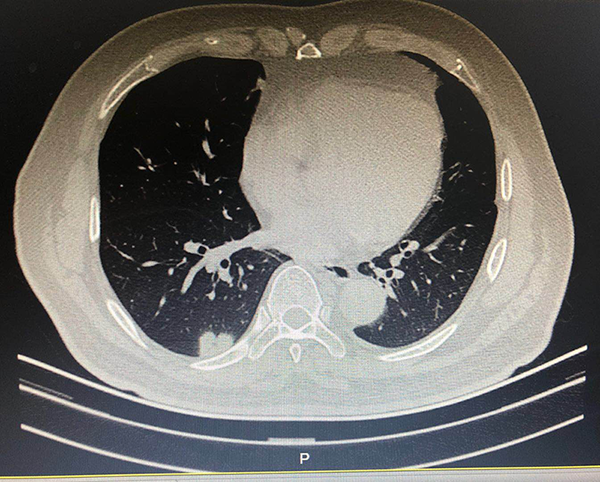

故事二、肺部磨玻璃结节别纠结

徐先生(化名)被查出肺部磨玻璃结节已有数月,且有三个——最大的约7mm,最小的5mm左右。自此,他陷入了惶惶不安,四处寻医,遍查医典,掌握了十分丰富的与肺部结节相关的医学知识。但他还是无法作出决定——开刀,或不开刀?

后经过王剑飞的一番分析与开导,徐先生终于决定手术,术后诊断——最大的是微浸润癌,其余2个是原位癌。虽然从预后看,开刀早晚差别不大,但徐先生终于安心了,又能轻松面对生活了。而对于王剑飞能想病人所想,细心考虑每一个患者的顾虑,徐先生感到十分暖心及感激。

转移前手术切除,在最大限度保留健康肺组织同时尽可能彻底切除病变肺组织,人性化考虑结节患者的处理策略——是该中心始终坚持的三大原则,他们希望每一位患者都能获得充分的诊疗,放心随访、安心开刀,能真正再次拥抱美好生活。